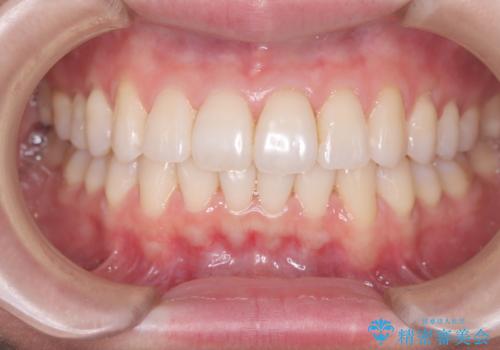

前歯の叢生は解消され、自然で調和の取れた歯並びが得られました。

「歯をほとんど削らずにきれいになった」と、患者様にもご満足いただけました。